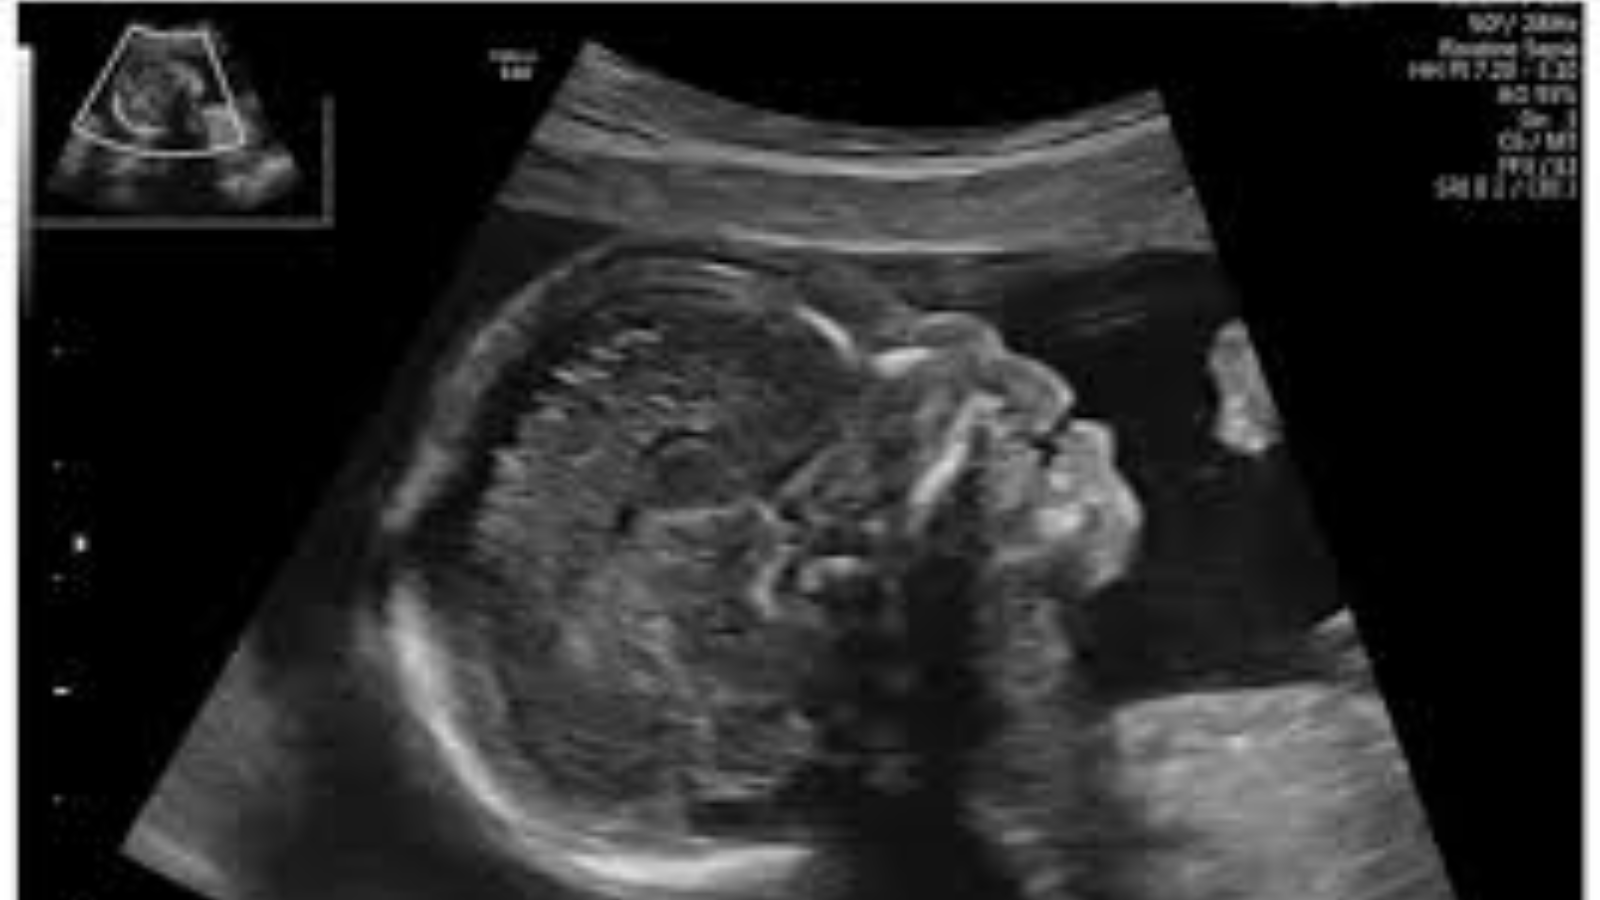

Chiều dài xương mũi của thai nhi là một chỉ số quan trọng trong sàng lọc trước sinh, giúp bác sĩ đánh giá nguy cơ mắc hội chứng Down. Hội chứng Down là một rối loạn bẩm sinh phổ biến, liên quan đến bất thường về số lượng nhiễm sắc thể, gây ảnh hưởng đến sự phát triển thể chất và trí tuệ của trẻ.

Trong tam cá nguyệt đầu tiên, nguy cơ hội chứng Down thường được đánh giá thông qua các yếu tố như tuổi của mẹ, độ mờ da gáy, chỉ số sinh hóa và xét nghiệm huyết thanh. Độ chính xác của các xét nghiệm này có thể đạt từ 85% đến 90%. Một trong những đặc điểm hình thái điển hình ở thai nhi mắc hội chứng Down là xương mũi ngắn hoặc không thấy xương mũi trên siêu âm. Do đó, đo chiều dài xương mũi đã được đưa vào quy trình siêu âm thai sàng lọc nhằm tăng khả năng phát hiện sớm nguy cơ bất thường nhiễm sắc thể.

Trong quá trình phát triển bào thai, xương mũi thường bắt đầu hình thành vào khoảng tuần thai thứ 12. Việc đo chiều dài xương mũi thường được thực hiện khi chiều dài đầu mông của thai nhi nằm trong khoảng từ 64 – 75 mm và chỉ số này tiếp tục được theo dõi định kỳ đến khoảng tuần thứ 28 – 32 của thai kỳ.

Siêu âm ở tuần thứ 12 có thể phát hiện hai bất thường chính liên quan đến xương mũi như không quan sát thấy xương mũi (bất sản xương mũi) hoặc xương mũi ngắn hơn so với tuổi thai (thiểu sản xương mũi). Nếu các dấu hiệu này đi kèm với các bất thường hình thái khác hoặc kết quả sàng lọc sinh hóa như Double test, Triple test hoặc xét nghiệm NIPT cho thấy nguy cơ cao, bác sĩ có thể chỉ định thực hiện chọc ối để xác định chính xác tình trạng nhiễm sắc thể. Trong trường hợp kết quả chọc ối không phát hiện bất thường, thai phụ có thể yên tâm tiếp tục theo dõi thai kỳ theo đúng lịch hẹn.